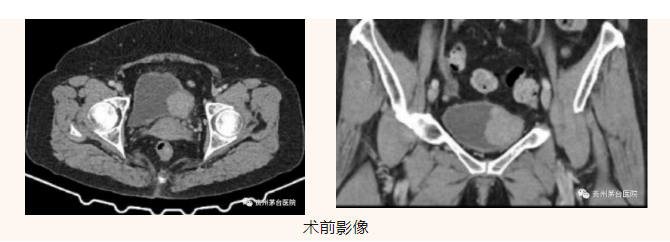

患者因“血尿13天”入院,盆腔增强CT检查发现膀胱左后壁一占位性病变,考虑膀胱肿瘤(大小约3.5*3.6*3.8cm)。

经贵州茅台医院泌尿外科术前讨论分析,考虑膀胱巨大恶性肿瘤,经与患者及患者家属充分沟通同意后,行经尿道膀胱肿瘤电切术,术后病理结果提示:1、(膀胱肿瘤电切组织)高级别乳头状尿路上皮癌;2、送检平滑肌组织内未见肿瘤。患者术后恢复良好,已平稳出院。